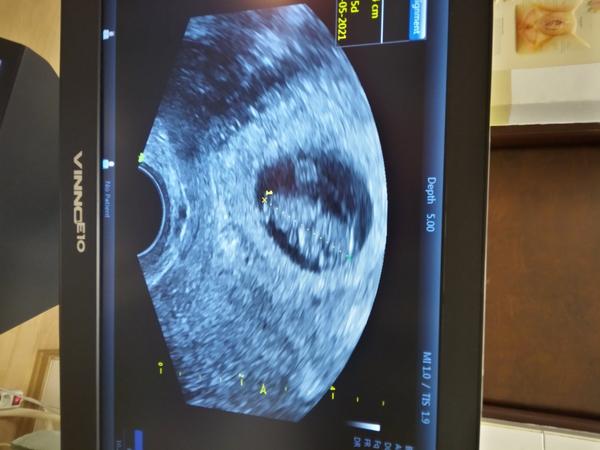

Ahoj. Ja mam tiez podobnu skusenost. Akurat som tu aj pridala prispevok, nech mi poradia ci je to tym. Mne dr zistila dvojky z krvy. Potom ich bolo krasne vidiet aj na ultrzvuku ako biju srdiecka, ale o dva tyzdne uz bilo iba jedno :( to bolo pred tyzdnom a vcera ma chytili krce aa dnes uz tmave spinenie. Tak ma hned aj vypisala s max.kludovym rezimom. Ze asi sa nedokazalo, vstrebat to dvojcatko, tak musi vyjst takto von, ale ze je riziko aby nestiahlo aj to zdrave.. tak som z toho na nervy.. v utorok mam mat prvy 3d ultrazvuk..to bude dlhocizny vikend. Ja ale myslim podla toho ako vyzerali v 8.tt moje, ze to tvoje bude mat vedla seba len vacok. Drzim prsty.